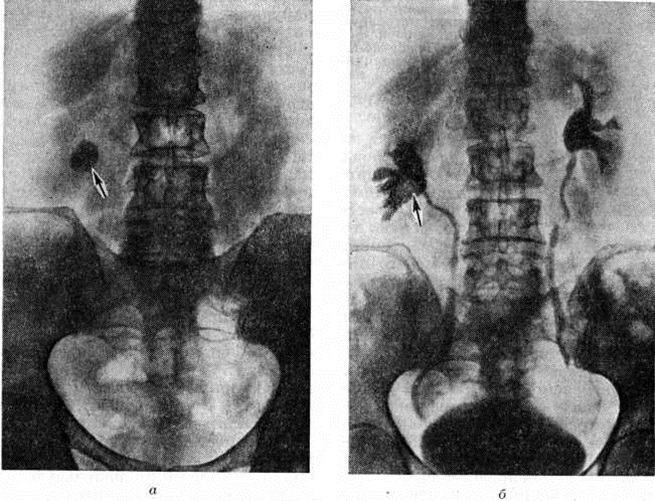

Рентгенологические метод является основным в диагностике Почечнокаменная болезнь Он позволяет выявить не только наличие камней, но и установить их форму, величину, локализацию, структуру, а также получить представление об изменениях в анатомо-функциональном состоянии почек и мочевых путей. Исследование начинают с обзорной рентгенографии брюшной полости, начиная от ThXl до лонного сочленения. Обнаружение на обзорной рентгенограмме тени, подозрительной на конкремент, не требует дифференциальной диагностики только в случае коралловидного камня, являющегося слепком чашечно-лоханочной системы (рисунок 2). Камни почечных чашечек представляют собой их слепки или имеют неправильную, округлую форму; камни почечной лоханки часто округлые или треугольные; камни мочеточника — цилиндрической, веретенообразной или неправильной формы. При аномалиях мочевых путей конкремент может находиться вне обычной локализации почек и других органов мочеполовой системы. Обнаружение камня на снимке зависит от его размеров, химический состава и локализации. Наиболее интенсивное изображение дают оксалаты, затем камни смешанного состава и фосфаты. Оксалаты имеют шиповидные, фестончатые контуры и напоминают тутовую ягоду. Коралловидные камни чаще всего компактны, но могут быть слоистыми, как и остальные конкременты смешанного состава, иногда они достигают гигантских размеров. Слоистое строение камней на рентгенограммах обусловлено различной проницаемостью для рентгеновского излучения составляющих их солей. Около 10% камней с низким атомным весом (ураты, белковые, цистиновые и ксантиновые камни) не видны или дают неотчётливую тень. Особенно трудно выявить камни, проецирующиеся на костный скелет (ребра, поперечные отростки позвонков, крестцово-подвздошные сочленения). Для их обнаружения производят прицельные снимки в косых и атипичных проекциях, томо или зонографию. Томография (смотри полный свод знаний), применяемая самостоятельно или в сочетании с контрастными исследованиями, показана при недостаточной подготовке больного к рентгенологическое исследованиям, почечной колике, сопровождающейся парезом кишечника, или при малых размерах камней. Поскольку при Почечнокаменная болезнь довольно часто конкременты самопроизвольно отходят из чашечно-лоханочной системы, они могут проецироваться по ходу мочеточника паравертебрально, имеют тенденцию задерживаться над одним из его анатомических сужений. Наиболее важные сведения о принадлежности выявленной тени к мочевым путям, о локализации камня, вызванных им нарушениях функции почек, уродинамики, анатомического состояния мочевых путей (гидрокаликоз, пиелэктазия, гидроуретеронефроз — расширение чашечек, лоханки, мочеточника и почки) выявляются при экскреторной урографии (рисунок 3, б) с предварительной обзорной рентгенографией (рисунок 3, а). Она позволяет установить вид лоханки (открытая или закрытая, внутрипочечная или внепочечная), состояние лоханочно-мочеточникового сегмента (смотри полный свод знаний: Пиелография). Обычно рентгенопозитивный конкремент определяется в мочевых путях, но иногда его изображение перекрывается, как бы тонет на фоне контрастированной мочи, особенно при небольшом камне или малой интенсивности его изображения. При рентгенонегативных камнях виден дефект наполнения мочевых путей (в том числе и лоханки) с чёткими контурами (рисунок 4). В отличие от опухоли лоханки в косых проекциях вокруг камня сохраняется ободок контрастного вещества. Обычно при камнях лоханки, достигающих в диаметре 3 сантиметров и более, наблюдаются пиелэктазия и гидрокаликоз. Произведённые в процессе экскреторной урографии телевизионная пиелоуретероскопия в сочетании с кинематографией или видеомагнитофонной записью изображения позволяют оценить нарушения тонуса и моторной функции верхних мочевых путей при камнях, отличить спастические, функциональный процессы от органических. Если спустившийся в мочеточник камень частично закрывает его, то отмечаются расширение мочеточника и лоханки (пиелоуретерэктазия) выше уровня расположения конкремента. На экскреторных урограммах, произведённых во время почечной колики, выявляется увеличенная почка с усиленным нефрографическим эффектом без контрастирования чашечно-лоханочной системы и мочеточника — так называемый большая белая почка. Такая рентгенологическое картина указывает, что функция почки сохранена. При длительной полной блокаде камнем (более 3—4 недель) функция почки из-за атрофии снижается и может полностью утрачиваться. На экскреторных урограммах, произведённых после почечной колики, иногда наблюдается проникновение контрастированной мочи за пределы мочевых путей, а также лоханочно-почечный рефлюкс. Ретроградную пиелоуретерографию с жидким контрастным веществом или кислородом производят только при значительном снижении функции почек, при сомнении в диагнозе, особенно в тех случаях, когда при экскреторной урографии не выявляется рентгенонегативный камень. Рентгенографию мочеточника после введения в него катетера производят в прямой и косой проекциях. Если при этом тень, подозрительная на камень, на обоих снимках находится рядом с катетером или сливается с его тенью, то диагноз Почечнокаменная болезнь не вызывает сомнений. Тень, не относящаяся к мочеточнику, определяется на некотором расстоянии от катетера. На ретроградных пиелограммах с жидким контрастным веществом небольшой концентрации рентгенонегативные камни выявляются в виде дефекта наполнения. Особенно демонстративными такие камни становятся при пневмопиелорентгенографии или пневмопиелотомографии (рисунок 5). С помощью ретроградной уретерографии удаётся выявить рентгенонегативный камень в мочеточнике, верхние границы дефекта при этом имеют вогнутую форму (рисунок 6).